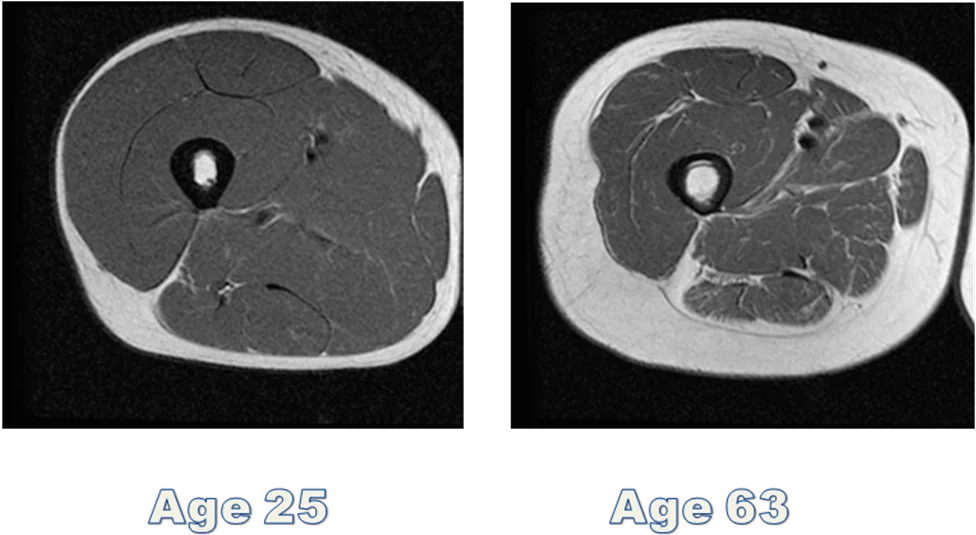

La masa corporal magra va a disminuir entre los 35 y los 70 años, esto se debe principalmente a la pérdida de masa muscular esquelética y a la progresiva disminución del número y el tamaño de las fibras musculares.

El músculo se va perdiendo por la disminución en el número de fibras musculares, especialmente las de tipo II (son las fibras blancas que se encargan de la contracción rápida) y, en menor medida, a la atrofia (es la disminución del tamaño de un órgano por pérdida de masa) de las mismas.